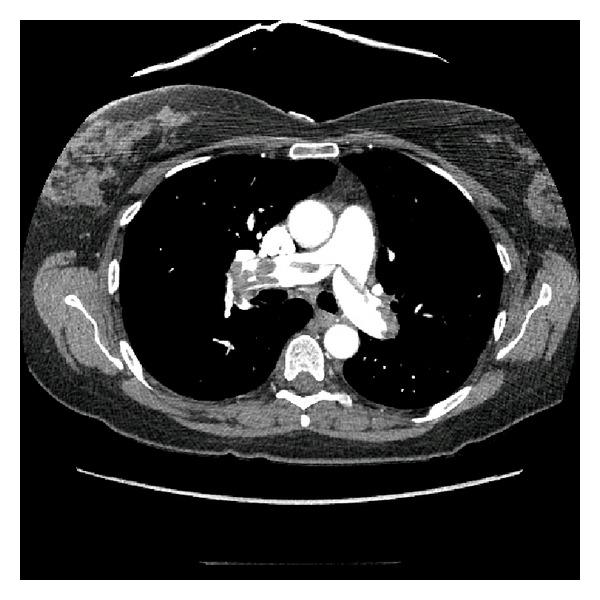

Optimal management of the critically ill patient in shock requires rapid identification of its etiology. We describe a successful application of an emergency physician performed bedside ultrasound in a patient presenting with shock and subsequent cardiac arrest. Pulmonary embolus was diagnosed using bedside echocardiogram and confirmed with CTA of the thorax. Further validation and real-time implementation of this low-cost modality could facilitate the decision to implement thrombolytics for unstable patients with massive pulmonary embolism who cannot undergo formal radiographic evaluation.

对休克危重症患者进行最佳管理需要快速确定其病因。我们描述了一名急诊医生在一名出现休克并随后发生心脏骤停的患者中成功应用床旁超声的案例。通过床旁超声心动图诊断为肺栓塞,并经胸部CTA证实。这种低成本模式的进一步验证和实时应用,可为无法接受正式影像学评估的大面积肺栓塞不稳定患者实施溶栓治疗的决策提供便利。